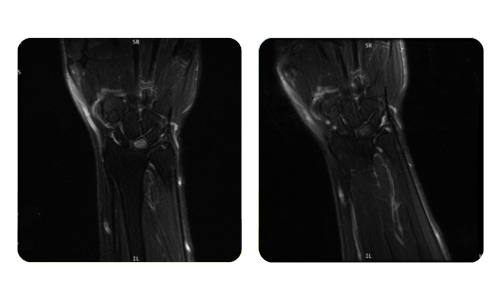

The progress of our patients, measured before and after hyperbaric therapy, reflects the efficiency and positive impact of the treatment. Discover documented results of hyperbaric therapy at Hyperbarium Oradea clinic, based on clinical evaluations and objective data that highlight significant improvements in various conditions.